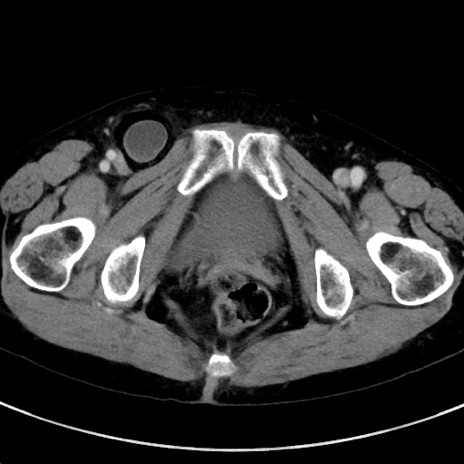

症例23(横断像)

【症例】70歳代女性

【主訴】下腹部痛・嘔吐

【現病歴】2日前より腹痛あり。昨日嘔吐あり。症状改善しないため来院。

【既往歴】胃GISTに対して胃部分切除後。

【身体所見】BT 37.1℃、BP 128/77mmHg、腹部:平坦・軟、下腹部に圧痛あり。

【データ】WBC 10200、CRP 0.31